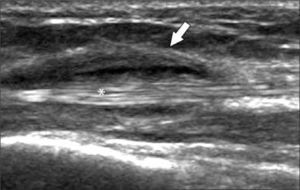

Ecografía muscularSu indicación más frecuente es para evaluación de desgarros, con distintas manifestaciones y clasificaciones dependiendo del mecanismo, del grado de lesión, la localización y la anatomía de los distintos músculos (1, 5, 6).

Los más frecuentes son los indirectos por distensión de músculos que atraviesan dos articulaciones.

Se puede encontrar desgarros desde bajo grado fibrilares, parciales fasciculares, hasta completos, con presencia variable de hematomas o colecciones líquidas de distinto tamaño. Según su localización en el músculo pueden ser intrasustancia, periféricos miofasciales o en la unión miotendínea (figura 12). En el caso de trauma directo puede haber rotura por compresión contra el hueso o laceración por herida penetrante.

Cabe mencionar que en ocasiones desgarros pequeños pueden no ser evidentes a la ecografía en las primeras 24-48 horas, por lo cual si la clínica es concordante y el US negativo, se sugiere una re-evaluación ecográfica posterior.

Según la evolución, en el tiempo se pueden encontrar cicatrices fibrosas, zonas de re-desgarro o hernias musculares por rotura de la fascia.